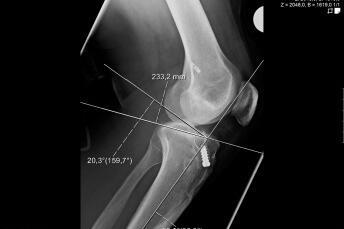

Pathological deformities of the upper or lower leg bones result in incorrect loads on the knee joint, but they can also result in restricted movement. A precise axis analysis, which we can perform with the help of a computer programme, shows us the location of the deformity. This enables us to carry out a correction at the site of the malposition by cutting through the bone (osteotomy) and then stabilise this correction with stable-angle plates. Partial weight-bearing and free mobility is usually possible immediately. Osteotomies close to the knee joint on the upper leg (femur) and lower leg (tibia) have proven successful in the prevention and treatment of osteoarthritis and in the treatment of ligament instabilities.